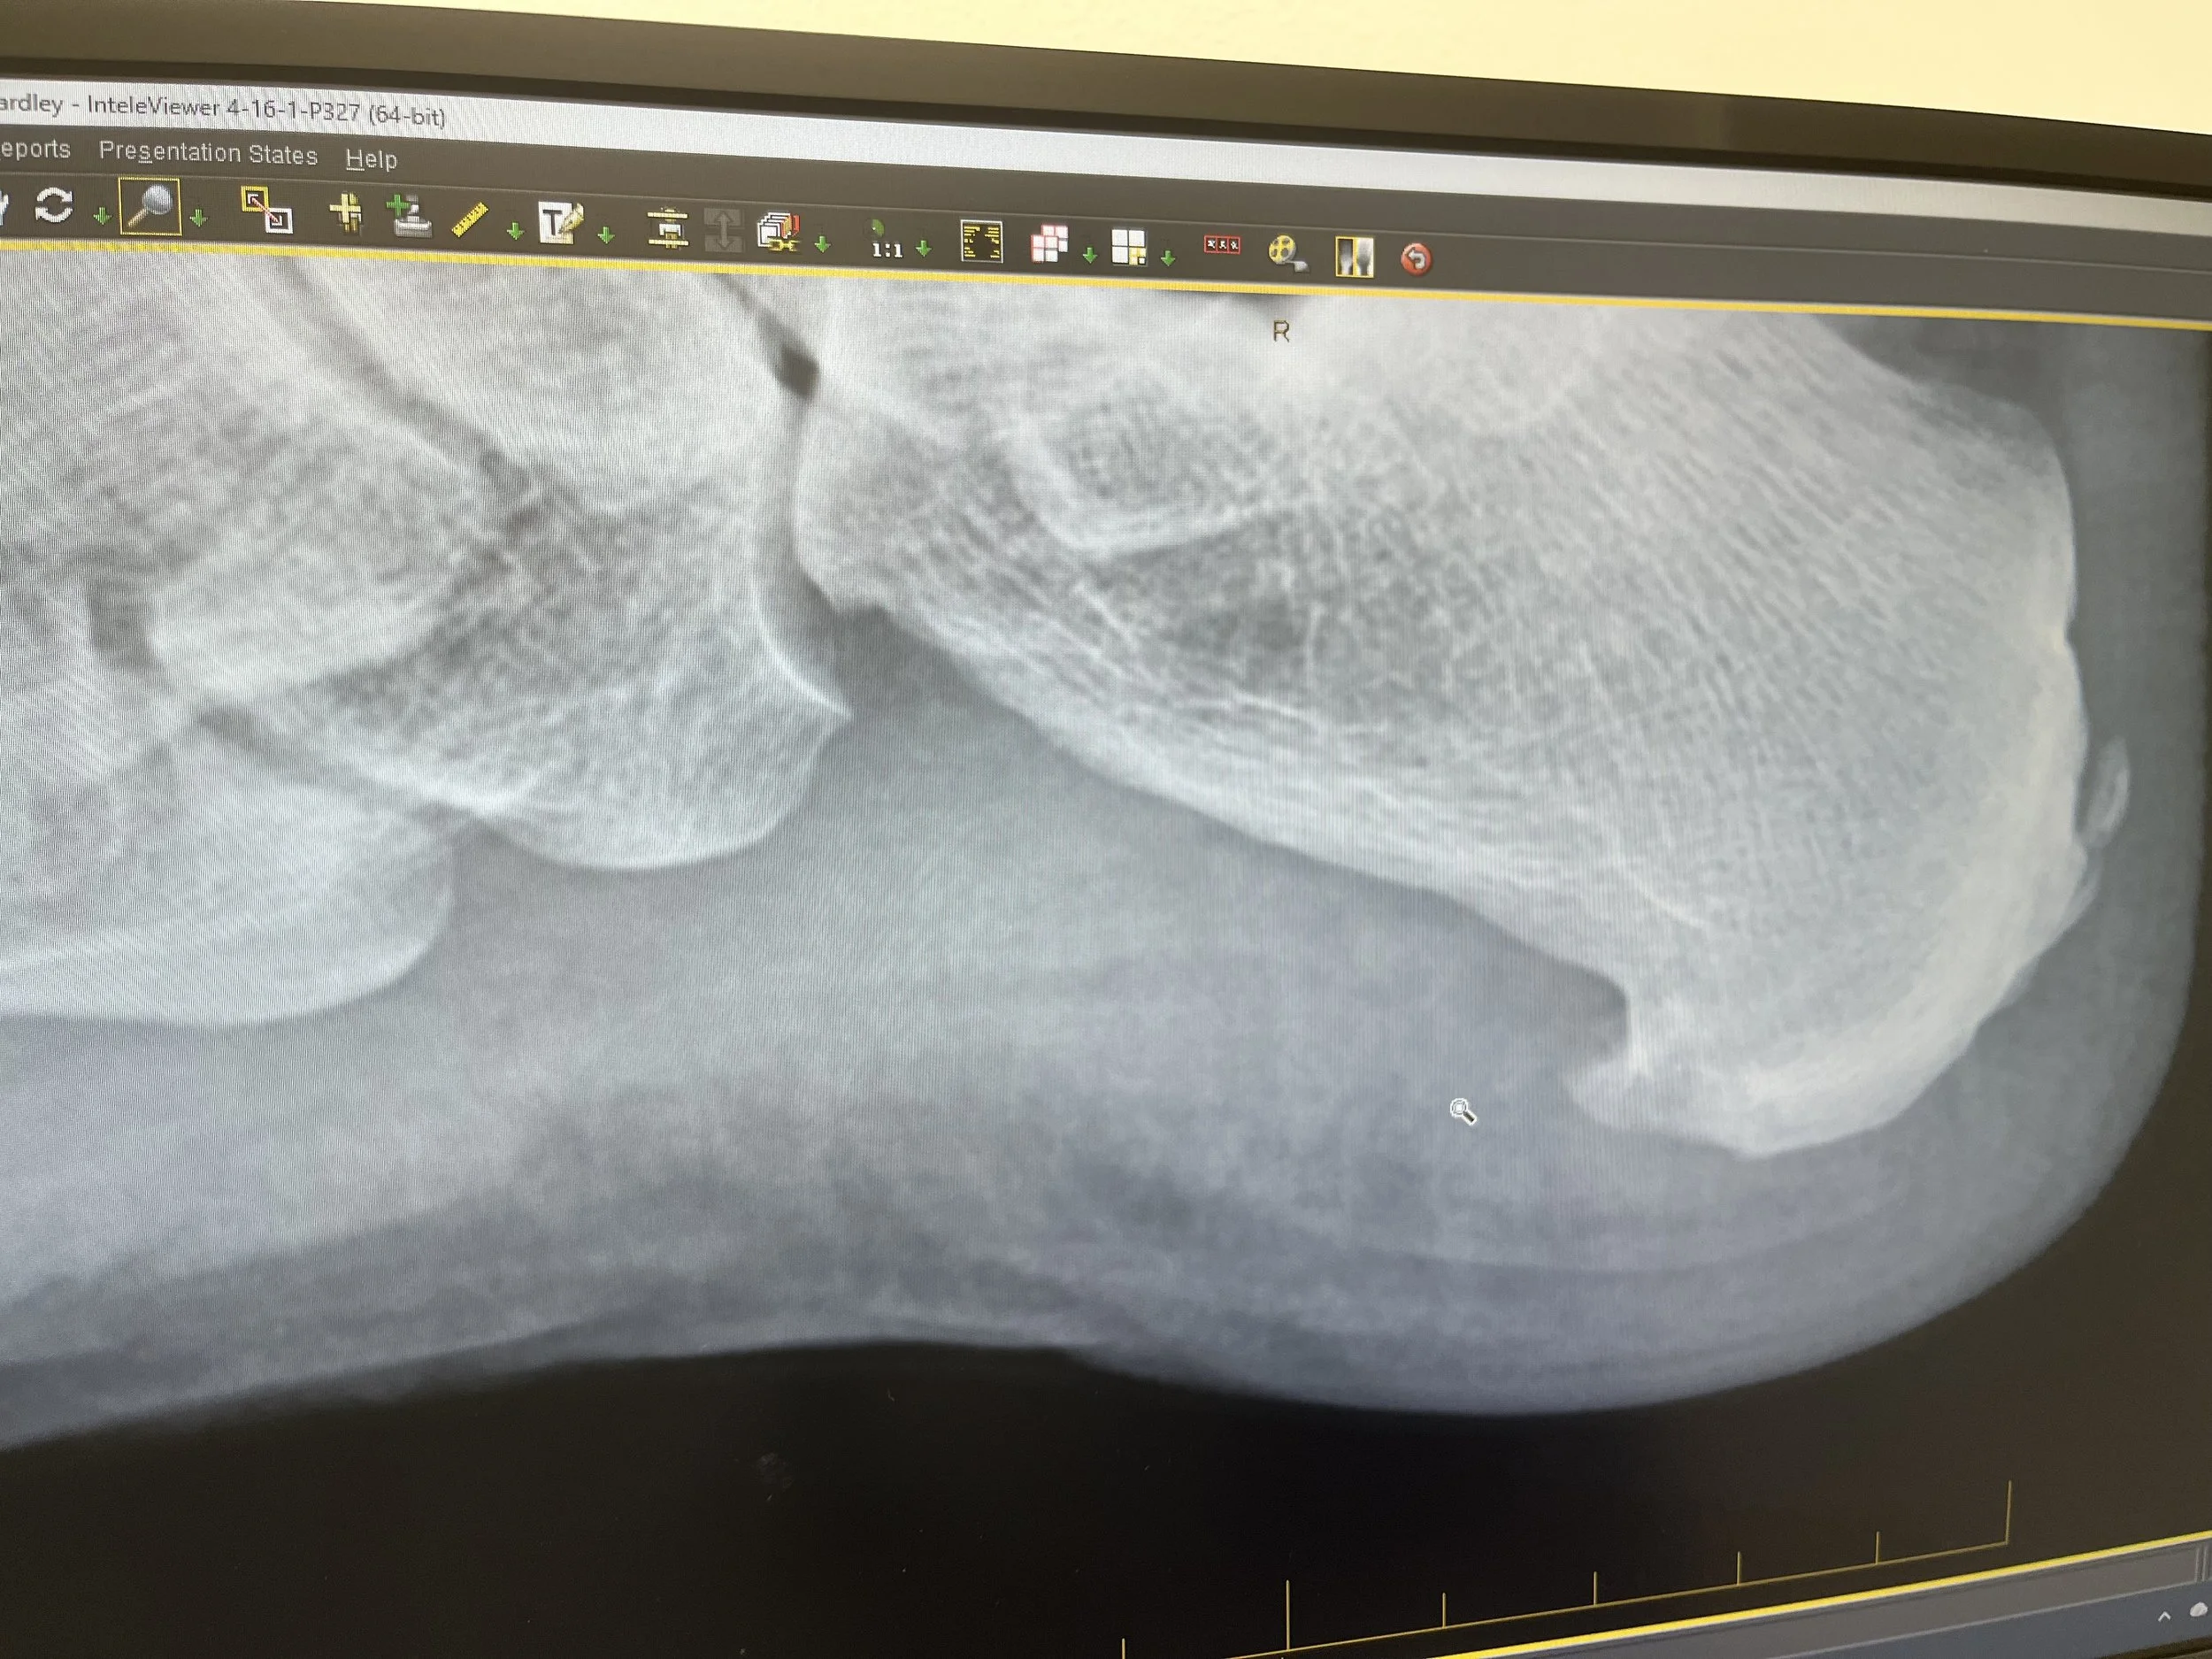

Greetings from the pickleball kitchen! It's been a while since I've aired my grievances (I mean, shared my thoughts) about the game. I'm currently on a self-imposed two-week "vacation" from the court, all thanks to what I'm pretty sure is a case of plantar fasciitis – because apparently, my feet decided to join the "over-the-hill" club without my permission. It's a common injury, especially for those of us who enjoy a good run or a vigorous court sport, or, you know, just generally exist past a certain age. I did manage to have an X-Ray which shows I have a heel spur. Fun.

Sigh…Heel Spur